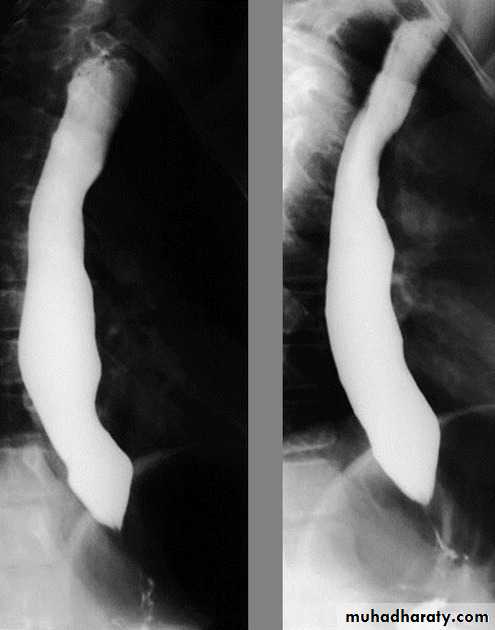

Esophageal diseases